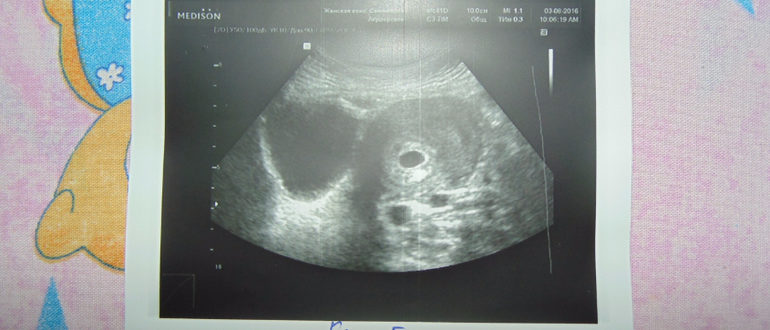

Выделения после узи

Последствия УЗИ у женщин Гинекологи отдают предпочтение трансвагинальному УЗИ, которое дает четкую картину состояния органов малого таза. Оно может назначаться беременным женщинам, так как помогает проследить за развитием…